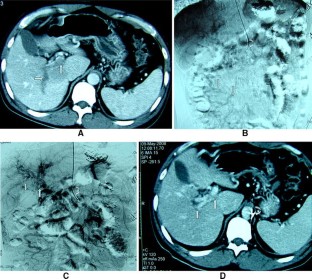

Fig. 1

Fig. 2

Fig. 3

Fig. 4